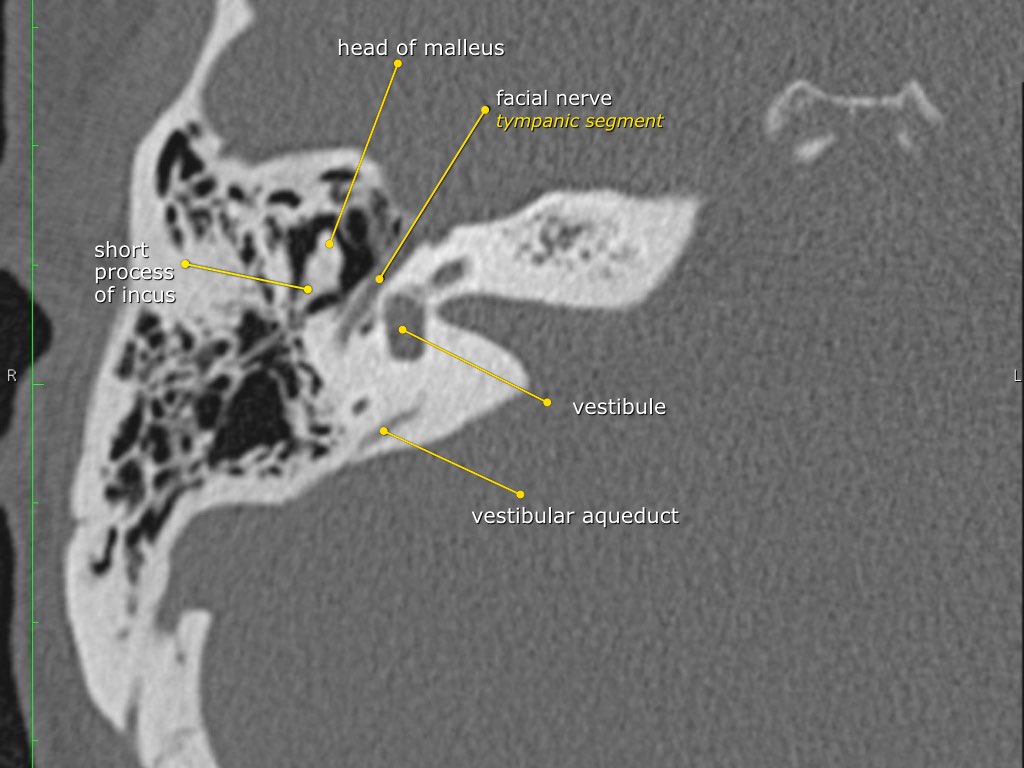

Dây thần kinh mặt

Đoạn mê nhĩ của dây thần kinh mặt xuất phát từ ống tai trong, chạy gần như vuông góc với trục dài của xương đá, gập góc nhọn về phía trước để đến hạch gối (geniculate ganglion).

Tại hạch gối, dây thần kinh mặt tạo thành một khúc quặt hình chữ U (genu thứ nhất của dây thần kinh mặt) để chạy ra phía sau theo đoạn nhĩ dọc theo thành trong của thượng nhĩ.

Hang bào chũm (Antrum)

Hang bào chũm là một tế bào khí lớn nằm phía trên và phía sau hòm nhĩ, thông với hòm nhĩ qua ngách hang (aditus ad antrum).